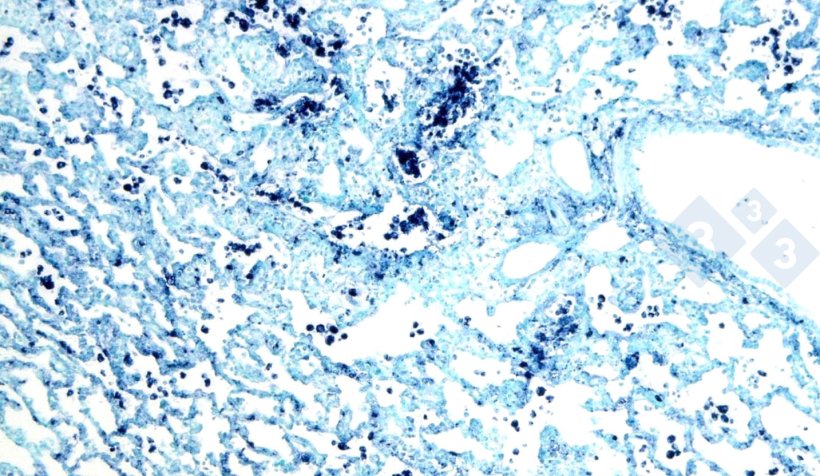

Les plus utilisées sont l'immunohistochimie (figure 3) et l'hybridation in situ (figure 4), qui permettent de détecter les agents pathogènes au niveau du site d'action, ce qui renforce leur rôle dans le contexte clinique et pathologique. Par ailleurs, il existe d'autres techniques (colorations histochimiques) qui ne suffisent pas à établir une étiologie spécifique, mais qui peuvent fournir des indices sur la cause (par exemple, la coloration de Groccot pour les champignons ou la coloration de Gram pour les bactéries gram-positives ou gram-négatives).

Figure 4 : Hybridation in situ pour le circovirus porcin 2 (PCV2) dans un poumon atteint de pneumonie interstitielle.